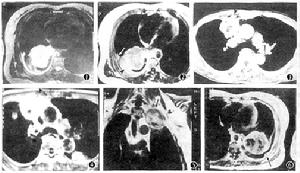

二、電子計算X線機體層顯象(CT)

CT的優點在於能發現X線進差不能顯示的解剖結果,特別對於位於在心臟後、脊柱旁溝和在肺尖、近膈面下及肋骨頭部位極有幫助。還可辨認有無肺門和縱隔淋巴結腫大。如縱隔淋巴結直徑大於20mm,腫瘤侵入最個脂肪間隙或包繞大血管,則基本不能手術。CT還能腫瘤有無直接侵犯鄰近器官。螺鏇CT對病灶大於3mm者多能發現。它對轉移癌的發現率比普通斷層高。

三、磁共振顯像(MRI)

MRI在肺癌的診斷價值基本與CT相似,在某些方面優於CT,但有些方面又不如CT。如MRI在明確腫瘤與大血管之間關係明顯優於CT,在發現小病灶(<5mm)方面由遠不如螺鏇CT。在鈣化灶顯示方面也很困難,且MRI易受呼吸偽影干擾,一些維持生命的設施如氧氣瓶、呼吸機等不能代入磁場。因此,病情為重或嚴重呼吸困難者,一般不宜選用MRI檢查。有心臟起搏器者為絕對禁證。因此,MRI只適用於如下幾種情況:臨床上確診為肺癌,需進一步了解腫瘤部位、範圍,特別是了解肺癌與心臟大血管、支氣管胸壁的關係,評估手術切除可能性者;疑為肺癌而胸片及CT均為陰性者;了解肺癌放療後腫瘤復發與肺纖維化的情況。